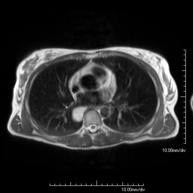

- Chest MRI

This non-invasive diagnostic procedure uses an electromagnetic field and radio waves (from a transmitter and receiver) to acquire high-definition anatomical images of the chest. It is a radiation-free procedure. It is indicated for lung lesions in which infiltration of the mediastinum or thoracic wall must be ruled out, to differentiate between solid and cystic chest lesions, etc. Sometimes paramagnetic contrast (gadolinium) must be used to complete the study.